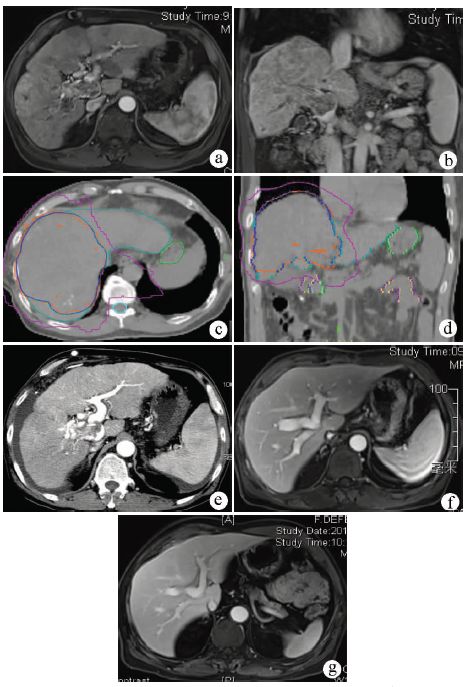

上海东方肝胆外科医院进行一项随机前瞻多中心的临床研究[4],比较肝细胞癌伴门静脉癌栓患者的术前新辅助放疗与不放疗的生存情况,放疗组82例,给予18 Gy/6次的新辅助外放疗;对照组82例,未行新辅助放疗。结果显示:新辅助放疗组的1、2年生存率分别为75.2%、27.4%,对照组分别为43.1%,9.4%,两组生存率有统计学差异(P<0.001)。新辅助放疗明显提高肝细胞癌患者的术后生存期。病例2是门静脉主干癌栓,经过新辅助放疗,癌栓从程氏Ⅲ型降为Ⅱ型,最后获得手术切除(图2)。

注:a,放疗前MRI检查,发现门静脉主干和右后支癌栓(箭头所示);b,放疗后3个月随访MRI,癌栓明显缩小,血供减少(箭头所示),患者获得切除机会。

图2 新辅助放疗后门静脉癌栓程氏Ⅲ型降为程氏Ⅱ型

注:a、b,MRI见门静脉主干、分支癌栓,肝内弥漫性病灶;c、d, CT扫描制定放疗计划,给予TOMO放疗50 Gy/25次,包括右叶及其门静脉主干;e,放疗后3周随访CT,门静脉癌栓明显缩小,但是腹水增多。于2011年9月28日接受肝移植。术后病理:肝内肿块14枚,最大位于肝右叶,5.5 cm×7.4 cm×3.5 cm,门静脉癌栓;f、g,移植术后5个月和6年随访MRI,无肝内复发,迄今存活8年。

图3 门静脉癌栓放疗后原位肝移植